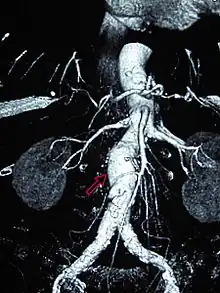

The diagnosis of an abdominal aortic aneurysm can be confirmed by the use of ultrasound. Rupture may be indicated by the presence of free fluid in the abdomen. A contrast-enhanced abdominal CT scan is the best test to diagnose an AAA and guide treatment options.[14]